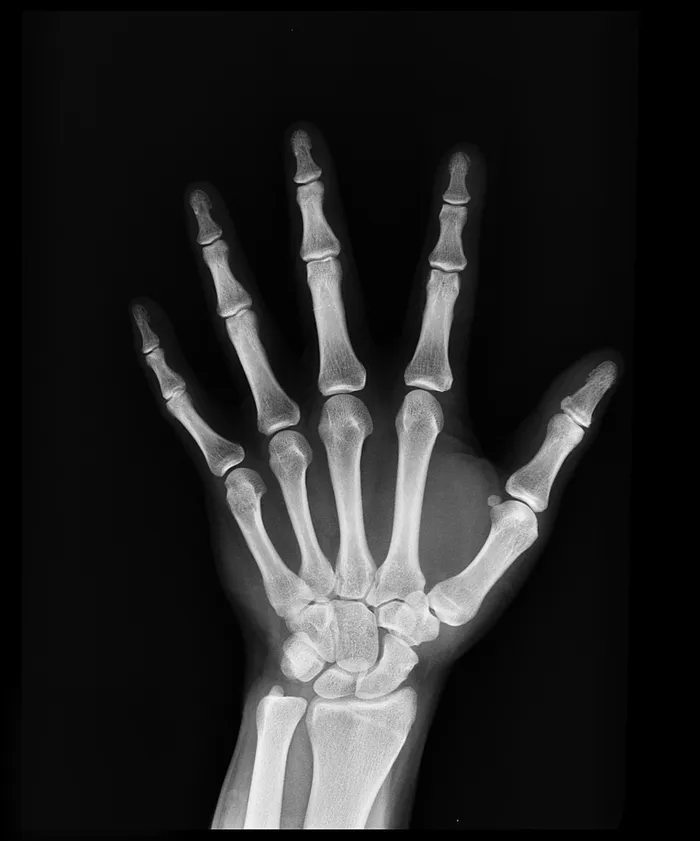

German scientist, Wilhelm Roentgen, was studying the path of electricity in 1895 when he noticed that the image was sticking to a paper and contained details not contained in an ordinary photograph. After making a few adjustments, he took the first x-ray of a human hand. He won the Nobel Prize in Physics for 1901.